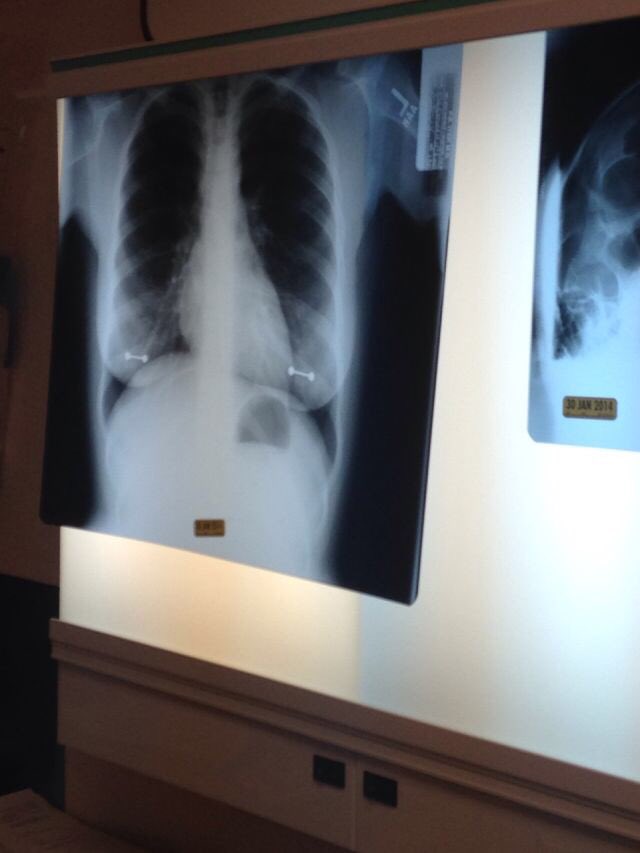

그러나 그녀가 병원에서 찍은 엑스레이 사진 한장 때문에 피어싱을 한 사실이 들통났다.

메트로에 따르면 시드니는 이미 척수공동증이라는 희귀병을 앓고 있었는데 이는 척수 안에 물이 찬 공동이 생기는 병으로, 시간이 지나면서 공동이 커져 척수신경을 손상시킨다고 한다.

시드니의 어머니는 이런 질병을 가진 딸을 위해 주기적으로 병원에 동행해 엑스레이를 확인한다고 한다.

그러나 이날 시드니가 피어싱을 빼는 것을 깜빡해 엑스레이에 피어싱이 고스란히 찍히고 말았다고 한다.